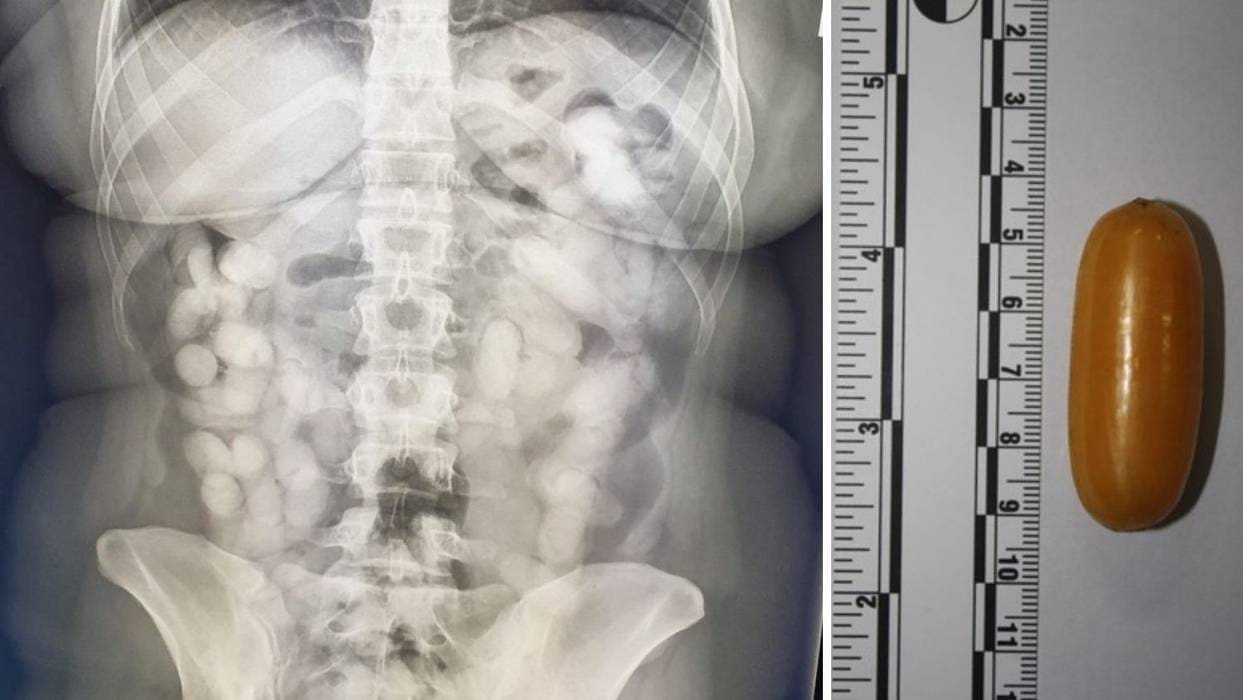

Brazilka je progutala čak 74 kapsule u kojima je bilo ukupno 990 grama kokaina. Detektirali su je pripadnici graničnog carinskog ureda Zračne Luke Zagreb.

"Počinju se slagati kockice paklenog plana 28-godišnje Brazilke. Ona se prije desetak dana ukrcala na avion u Sao Paolu i krenula prema Lisabonu, gdje je presjela u drugi avion i stigla u Zagreb", doznao je reporter Domagoj Mikić, koji je potvrdio i da je 990 grama kokaina bilo izuzetno visoke čistoće.

Zagreb je bio posljednje odredište osumnjičene, što znači da je droga trebala završiti na zagrebačkim ulicama, odnosno na ulicama Hrvatske.

"U ovih 76 kapsula bio je čisti kokain - dvostruka ili trostruka količina trebala je biti rasparčana na hrvatskom narko-tržištu", doznao je Mikić te dodao kako uhićenu mulu čeka zatvorska kazna do deset godina. Ona je iz bolnice prebačena u sjedište krim-policije u Heinzlovoj ulici u Zagrebu, gje je ispitana. Saslušana je i na tužiteljstvu te predana pritvorskom nadzorniku. Bit će zatraženo određivanje istražnog zatvora. Sudit će joj se i služit će kaznu u Hrvatskoj.